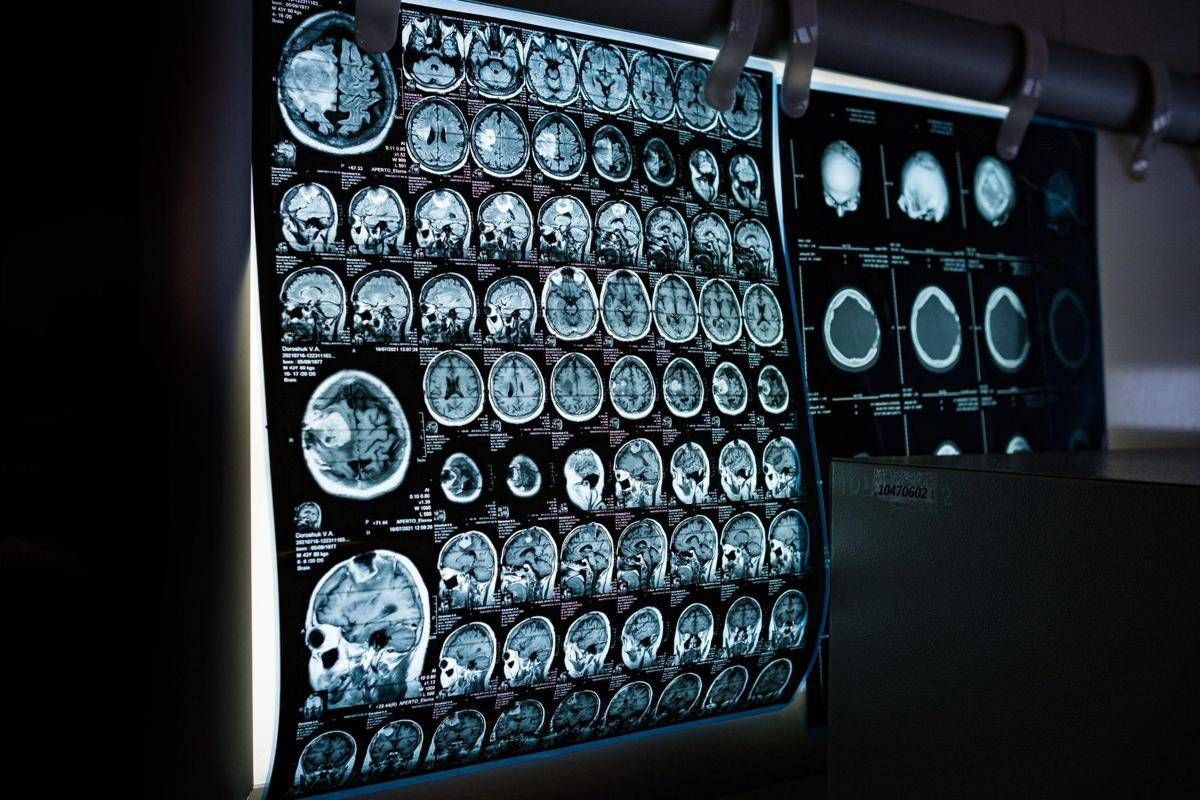

Uno spray nasale testato sui modelli animali potrebbe invertire l’invecchiamento del cervello con sole 2 dosi, riducendo drasticamente l’infiammazione cerebrale, ripristinando le centrali energetiche cellulari del cervello e migliorando così significativamente la memoria. Un processo di ringiovanimento che agirebbe nel giro di poche settimane per durare mesi.Â

E’ il risultato dello studio condotto dai ricercatori della Texas A&M University (Naresh K. Vashisht College of Medicine) negli Stati Uniti. Lo spray contiene minuscole particelle biologiche note come vescicole extracellulari (Ev), che agiscono come veicoli di consegna con a bordo un potente carico genetico, i microRna. Le sostanze aggirano lo scudo protettivo del cervello e viaggiano direttamente nel tessuto cerebrale, dove vengono assorbite. Arrivati a destinazione nelle cellule immunitarie residenti nel cervello, i microRna ‘spengono’ i sistemi noti per essere responsabili dell’infiammazione cronica nel cervello che invecchia.Â

Per spiegare il senso di questo processo, gli scienziati invitano a immaginare il cervello come un motore ad alte prestazioni: nel corso dei decenni questo motore non solo si usura, ma inizia anche a surriscaldarsi. Piccoli ‘focolai’ di infiammazione covano nelle profonditĂ del centro della memoria, creando una persistente nebbia mentale (brain fog) che rende piĂą difficile pensare, formare nuovi ricordi o persino adattarsi a nuovi ambienti, aumentando al contempo il rischio di disturbi come il morbo di Alzheimer. Questo processo a lenta combustione viene chiamato neuroinfiammazione. E per decenni si è pensato che fosse il prezzo inevitabile dell’invecchiamento. Ma il nuovo studio, pubblicato sul ‘Journal of Extracellular Vesicles’, suggerisce che l’ondata infiammatoria potrebbe essere reversibile.Â

Il team guidato da Ashok Shetty, distinguished professor dell’ateneo e associate director dell’Istituto di medicina rigenerativa, insieme ai ricercatori senior Madhu Leelavathi Narayana e Maheedhar Kodali, ha sviluppato lo spray nasale e ha verificato che a livello cellulare il trattamento ha ricaricato i mitocondri neuronali, ovvero le centrali energetiche che si trovano all’interno delle cellule cerebrali. La terapia ha dissipato la nebbia mentale e ha anche migliorato fisicamente la capacitĂ del cervello di elaborare e immagazzinare informazioni.Â